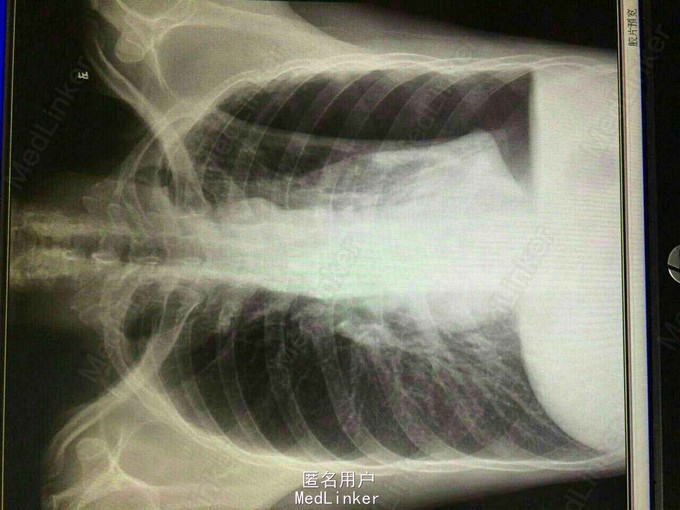

体查:浅表淋巴结无肿大,胸廓形态无畸形。左侧呼吸音弱。 胸片(2015-4-16):左侧液气胸,肺压缩约50%;左上肺纤维增殖灶;左上胸膜增厚粘连。 支气管镜检查:左右主支气管及各叶段支气管管腔通畅,粘膜光滑,分泌物不多,未见新生物及出血。 予以左胸腔闭式引流术。复查胸片(2015-4-22):左侧液气胸,与2015-4-16片对比,肺组织有所复张,肺压缩约22%。